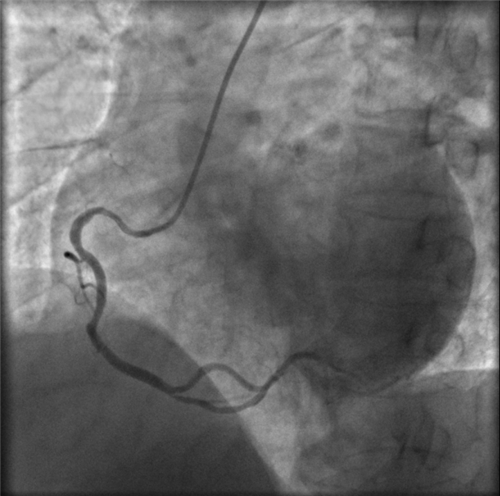

快速完成右侧桡动脉穿刺,上造影导管受阻后,行肱动脉造影,发现右侧肱动脉重度狭窄。

左主干完全闭塞

小心操作导丝及导管,艰难到达主动脉根部,但导管难以“到位”左冠口,“冒烟”见左主干居然完全闭塞了。

右冠近段严重狭窄,未见右向左的侧枝循环

再行右冠造影,右冠近段也严重狭窄,未见右冠向左冠的侧枝循环。